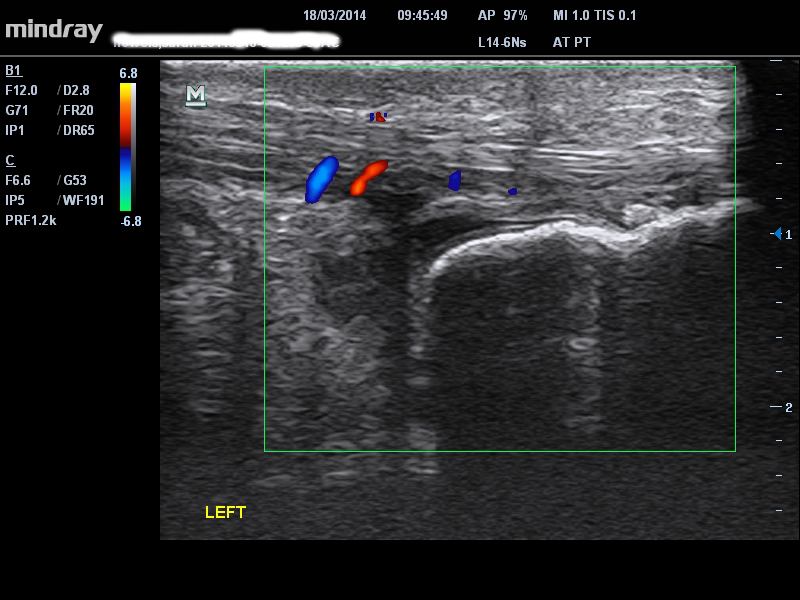

TENDINITIS DE LA INSERCIÓN

La principal diferencia en la tendinopatía de inserción es el sitio del dolor en la inserción distal del tendón de Aquiles ya sea alta (tuberosidad del calcáneo superior) o baja en el calcáneo distal. Hay un patrón similar en el comportamiento del dolor/rigidez matutina y en el ‘calentamiento’ en la tendinopatía de la porción media. El dolor de inserción alto debe diferenciarse de una bursitis retrocalcánea mientras que el dolor de inserción bajo suele ser del tendón. En la ecografía puede haber un espolón de tracción asociado con la inserción baja, pero esto no es necesariamente sintomático – ver espolón de tracción en la figura a continuación.

single-image

2 – patología del tendón de inserción alta con señal Doppler